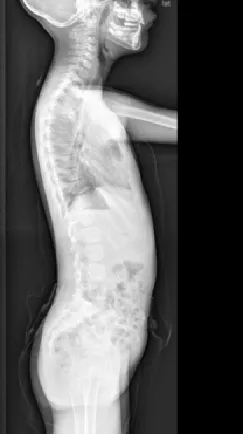

▲ 男,14岁,早发性脊柱侧弯、先天性脊柱畸形

▷退变性脊柱侧凸